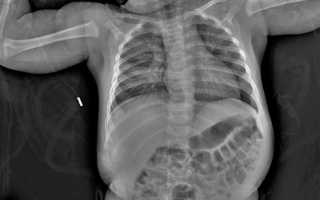

Атрезия легко выявляется по результатам рентгенограммы брюшной полости. У новорожденных диагностическое мероприятие определяет «двойной пузырь» при дуоденальной непроходимости, уровни жидкости при низкой непроходимости и кальцинаты, образующиеся при перфорации кишечника и мекониальном илеусе. Болезнь Гиршпрунга у новорожденных специалисты диагностируют по ответам ирригографии и биопсии кишки.

• рентгенографии с контрастированием – процедуры для выявления специфических признаков непроходимости кишечника.